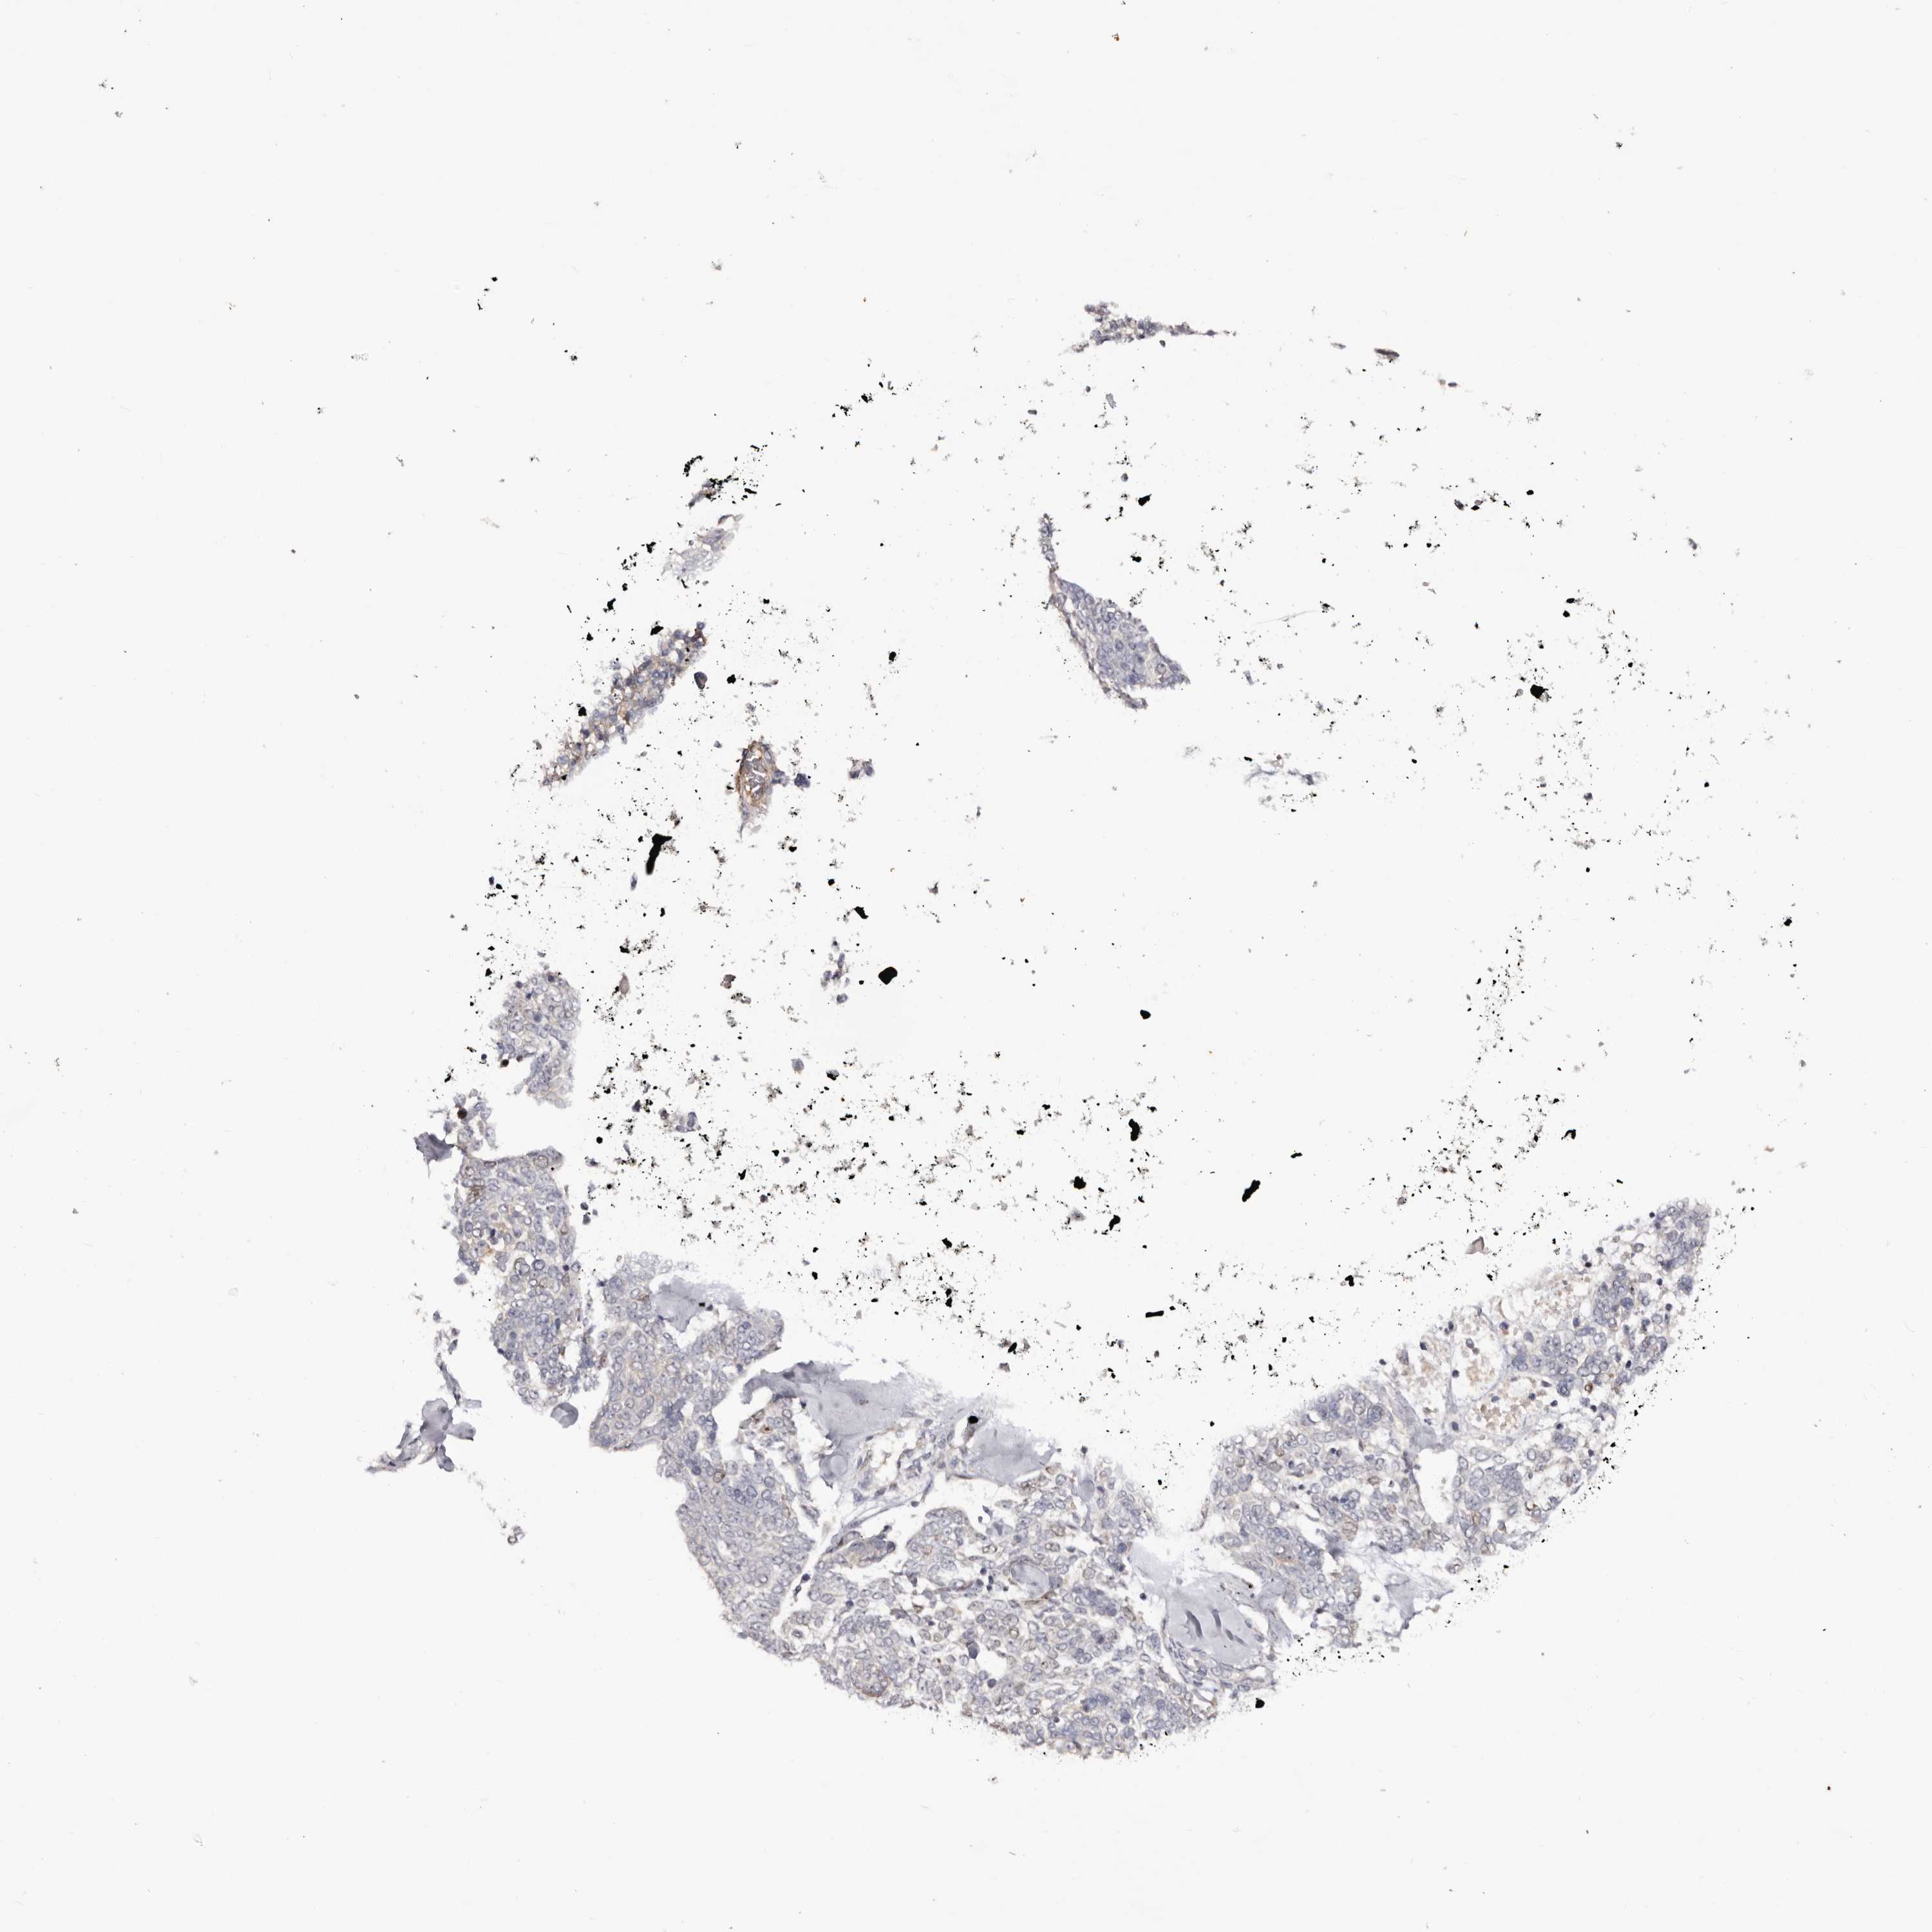

SKIN CANCER - Protein expressioni

A mouse-over function shows sample information and annotation data. Click on an image to view it in a full screen mode. Samples can be filtered based on level of antibody staining by selecting one or several of the following categories: high, medium, low and not detected. The assay and annotation is described here.

Each image is clickable and will lead to virtual microscopy that enables deeper exploration of all samples and also displays staining intensity scores, fraction scores and subcellular localization as well as patient and tissue information for each sample.

Antibody HPA028592

Squamous cell carcinoma, metastatic, NOS